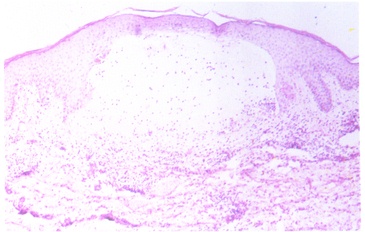

大疱性类天疱疮组织病理象示表皮下疱